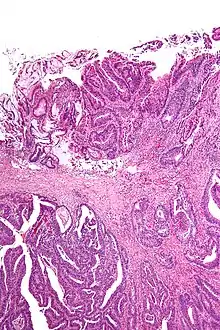

A resection margin or surgical margin is the margin of apparently non-tumorous tissue around a tumor that has been surgically removed, called "resected", in surgical oncology. The resection is an attempt to remove a cancer tumor so that no portion of the malignant growth extends past the edges or margin of the removed tumor and surrounding tissue. These are retained after the surgery and examined microscopically by a pathologist to see if the margin is indeed free from tumor cells (called "negative"). If cancerous cells are found at the edges (called "positive") the operation is much less likely to achieve the desired results.[1]: sections 1-2

Surgical margin in a surgery report defines the visible margin or free edge of "normal" tissue seen by the surgeon with the naked eye. Surgical margin as read in a pathology report defines the histological measurement of normal or unaffected tissue surrounding the visible tumor under a microscope on a glass mounted histology section.[4][5] A "narrow" surgical margin implies that the tumor exists very close to the surgical margin, and a "wide" surgical margin implies the tumor exists far from the cut edge or the surgical margin. Narrow surgical margin using the bread loafing technique suggests that residual cancer might be left due to false negative error. A surgeon often will perform a second surgery if a narrow surgical margin is noted on a pathology report.